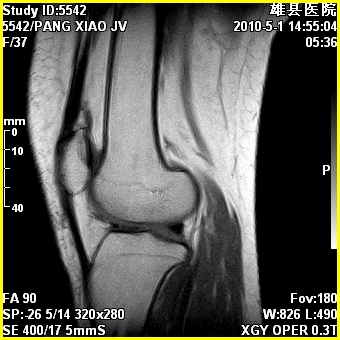

标题: MRI2894:患者右膝关节疼痛两月余,无明显外伤史 [打印本页]

标题: MRI2894:患者右膝关节疼痛两月余,无明显外伤史

右股骨下端前内侧类圆形异常信号,位于干骺端,呈长t1长t2改变,但信号不均,t1图上病灶中心见小片状稍高信号影,t2图上见散在稍低信号影,stir像呈高信号,因病灶较小,缺乏特征性改变,结合患者年龄及部位,考虑嗜酸性肉芽肿可能性大。胫骨关节面下的小囊状异常信号,如果一元论考虑则为嗜酸性肉芽肿,不过发生在这个部位的少见,二元论考虑为邻关节骨囊肿。半月板与前后交叉韧带均未见异常。

右股骨下端前内侧干骺端囊性良性病变,考虑 1内生软骨瘤 2骨囊肿 3肉芽肿。